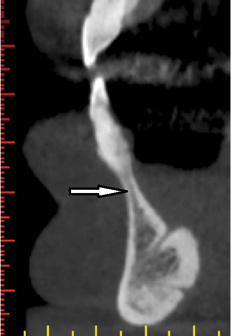

Fig 2. Inferior alveolar nerve: panoramic view. The third branch of the trigeminal nerve (mandibular branch) usually descends gently within the mandible (arrow). Other times, it may descend steeply within the mandible.

Figure 2